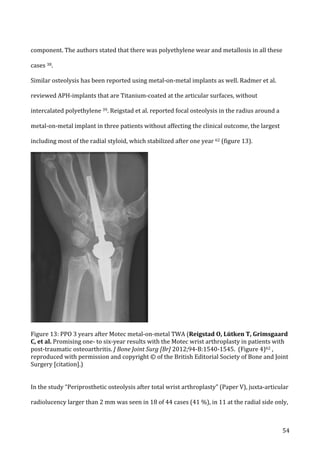

radiological

spots

for

the

measurement

of

radiolucency

on

digitalized

posteroanterior

radiographs